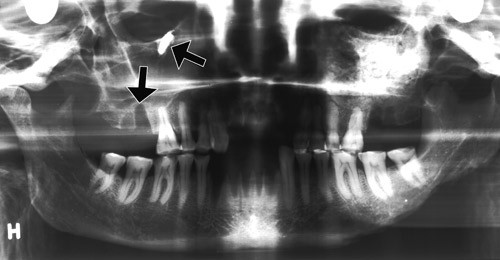

Bildet er fra en røntgenundersøkelse med ortopantomografisk teknikk av et middelalderkranium fra Oslo (De Schreinerske samlinger i Anatomisk institutt). Kraniet, fra en kvinne i alderen 40 – 60 år, har vært gravlagt ved kirken i Nonneseter kloster. Når hun levde, er ikke sikkert fastsatt. Klosteret omtales første gang i 1161 og synes å ha eksistert i flere tiår etter reformasjonen. Da Schweigaards gate ble opparbeidet i 1880-årene, «traf man saaledes flere skeletter, og i gadens nordre side 82 fod ifra dens sammenstød med Aaslo gade stod et hjørne af kvaderstene,» skrev antikvar Nicolaysen.

Overkjevens molarrøtter har nær anatomisk relasjon til sinus. Dette har stor klinisk betydning i odontologisk praksis. Bildet viser den nære forbindelsen mellom gulvet av sinus maxillaris, seksårsjekselen og den tomme alveolen etter tolvårsjekselen (pil). Høyt i sinus maxillaris, like under orbita, er det en tannrot «på avveier», dislokert til høyre sinus maxillaris (pil). Roten antas å stamme fra tolvårsjekselen.

Røntgenbildet viser ellers avslipning av tyggeflatene (okklusal abrasjon), ingen caries og et friskt periodontium. Det skiller seg en del fra tilsvarende røntgenundersøkte kranier fra andre gravplasser i middelalderens Oslo. I de fleste er den okklusale abrasjonen betydelig mer uttalt, og mange har mistet tenner som følge av marginal periodontitt. Det er mulig at forskjellen i dental helse kan ha sammenheng med bedre kosthold i Nonneseter kloster enn i den øvrige befolkningen.